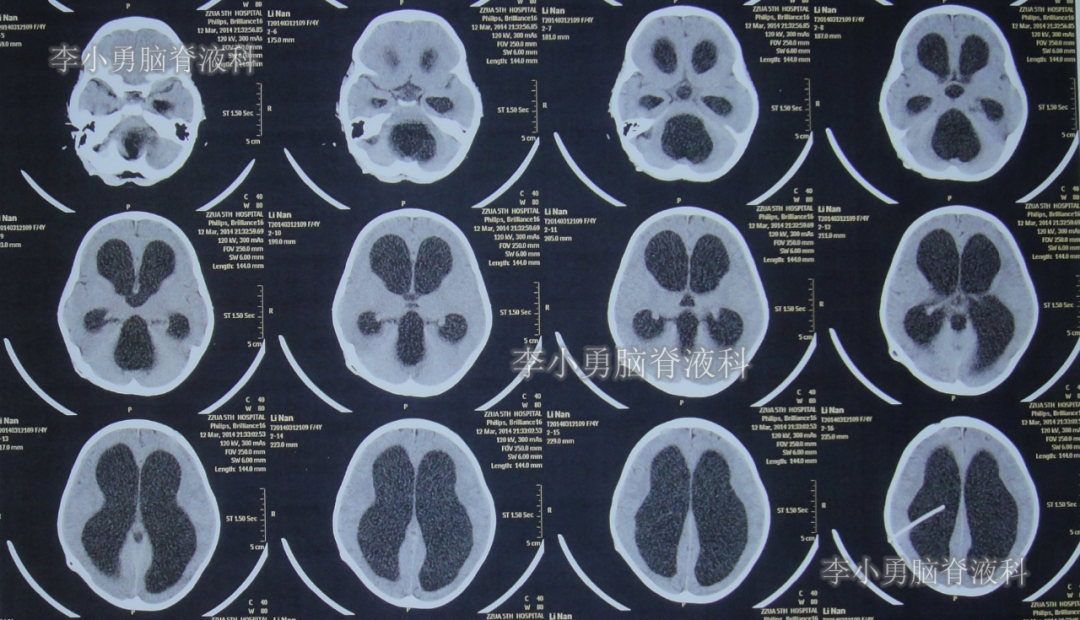

2021年2月18日入院时:头晕头痛,不爱讲话,走路时身体往左边歪斜,左腿单独站立不稳,偶有恶心呕吐(图-25);查头颅CT后考虑堵管(图-26)。

图-26:2021年2月18日入院时头颅CT

第2次住院治疗81天后症状完全消失,于2021年5月10日出院;出院时:言语变正常,走路时腿部变得有力量,走路时向左侧歪也变好,头痛头晕呕吐已完全消失。(图-27);出院时头颅CT示无异常(图-28)。

图-28:出院时头颅CT